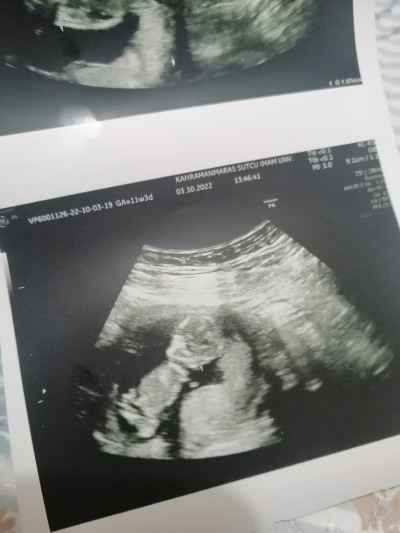

Kızlar kordon mu pipi mi

Kızlar anlayan var mi tipi mi kordon mu

Gebelik haftası

11

Canim onu doktor bile anlamiyo çıkıntı var ama kordon da olabilir diyolar hakkında hayırlısı olsun :)

Canım baya uzun görünyor o çıkıntı doğduğunda bile o kadar olmuyor sanırım kordon çünkü orası göbek deliğin olduğu yer bacak arası6daha aşağı